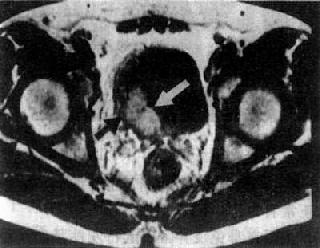

膀胱癌

图4-4-10 膀胱癌

膀胱腔内突起的肿块(白↓),

肿瘤已侵犯至壁外(黑↑)